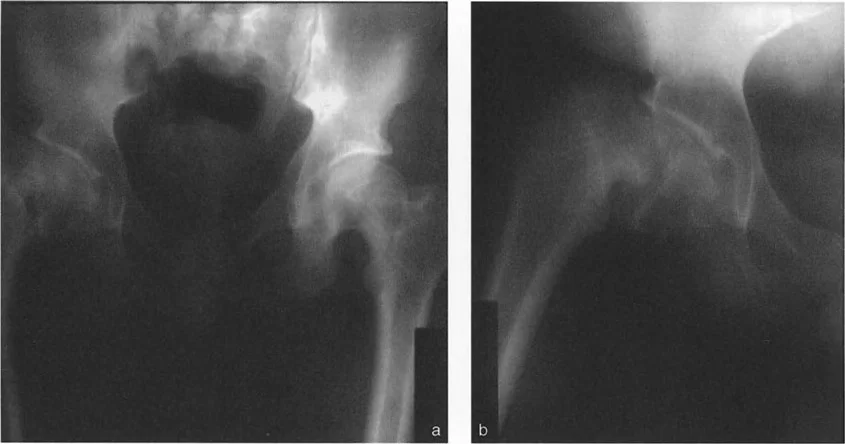

تُعد الأشعة السينية (X-rays) هي الخطوة الأولى والأساسية في التقييم الإشعاعي. ومع ذلك، فإن مفصل الورك معقد، وقد تتطلب بعض التشوهات صورًا إشعاعية خاصة.

- الأشعة السينية التقليدية: تُظهر صور الأشعة السينية الأمامية الخلفية (AP) والجانبية (Lateral) للورك العظام الرئيسية وتساعد في الكشف عن التشوهات الواضحة.

- صور الأشعة الجانبية عبر الطاولة (Cross-table lateral view): تُعد هذه الصورة حاسمة لتقييم الزاوية الأمامية لعنق الفخذ (ANSA) وتحديد التشوهات في المستوى السهمي. يُشدد الأستاذ الدكتور محمد هطيف على ضرورة الحصول على هذه الصورة بشكل صحيح، بحيث تكون موجهة بالنسبة لـ "المنظر الأمامي الحقيقي للورك" وليس الركبة، لتجنب ما يُسمى "فخ الالتواء".

فخ الالتواء (The Torsional Trap): إذا كان هناك تشوه التوائي شديد في عظم الفخذ (مثل زيادة في الميل الأمامي لعنق الفخذ)، فإن المنظر الأمامي الحقيقي للركبة (الرضفة متجهة للأمام) سيكون مختلفًا تمامًا عن المنظر الأمامي الحقيقي للورك. إذا قام فني الأشعة بالحصول على الصورة الجانبية عبر الطاولة بشكل عمودي على المنظر الأمامي الحقيقي للركبة بدلاً من الورك، فقد تظهر الزاوية الأمامية لعنق الفخذ وكأنها مُنثنية بشكل ملحوظ في الفيلم. هذا يخلق تشوه انثناء ثابت ظاهري للورك، وهو في الواقع خطأ ناتج عن الدوران وليس تشوهًا سهميًا حقيقيًا.

القاعدة التشخيصية: لا يتم تأكيد وجود تشوه انثناء ثابت حقيقي ناتج عن انحناء هيكلي في عنق الفخذ إلا إذا ظهرت الزاوية الأمامية لعنق الفخذ مُنثنية بشكل ملحوظ، وتطابقت الصورة الجانبية عبر الطاولة للورك تمامًا مع المنظر الجانبي الحقيقي للركبة.